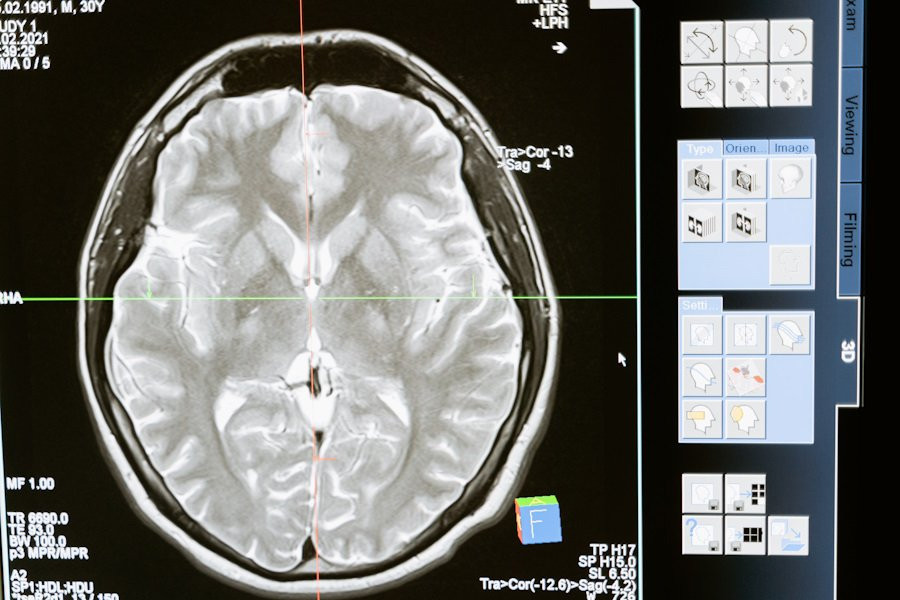

Транскраниальная магнитная стимуляция (TMS) - это метод медицинского исследования и терапии, который использует магнитные поля для воздействия на мозг человека. Этот метод немедленно и неинвазивно воздействует на активность мозга путем создания переменного магнитного поля над кожей головы.

Транскраниальная магнитная стимуляция используется в медицинских исследованиях для изучения функций мозга и их связи с различными психическими и нейрологическими состояниями, а так же для лечения некоторых болезней. Этот метод может помочь в восстановлении или модуляции активности мозга у пациентов с различными патологиями.